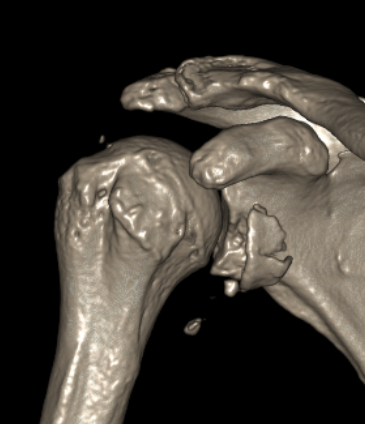

Type IA: Anterior glenoid rim fracture

Xray / CT